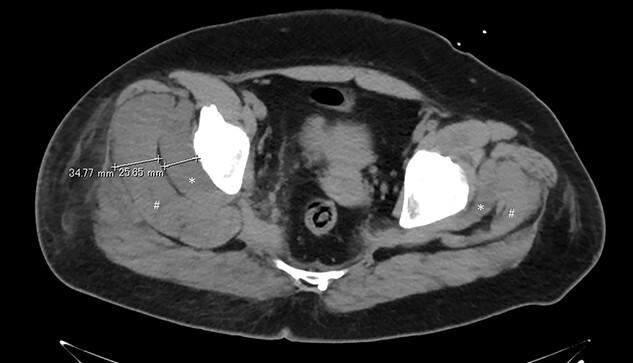

We present a case of a 42-year-old obese female with a body mass index of 38.4 kg/m. Laparoscopic tumor resection of a left nonfunctioning adrenal tumor was performed in the lateral jackknife position, and the operative time was over 5 h. After awakening, she complained right buttock pain, and we suspected bursitis due to the surgical position and decided to follow up the patient. On the second postoperative day, spontaneous pain worsened, and the computed tomography scan of the hip showed significant swelling of the gluteal muscles, which led us to suspect a gluteal compartment syndrome. Intramuscular compartment pressure was measured under general anesthesia at 72 mmHg, and a fasciotomy was performed. The symptoms improved promptly after surgery and completely disappeared 2 months after surgery. Although the gluteal compartment syndrome is a rare condition in which circulation is impaired by compression of the gluteal muscles, treatment should be initiated promptly before serious complications arise.

我们报告一例42岁肥胖女性病例,其体重指数为38.4kg/m²。在侧卧位折刀位进行了左侧无功能肾上腺肿瘤的腹腔镜肿瘤切除术,手术时间超过5小时。苏醒后,她主诉右臀部疼痛,我们怀疑是手术体位导致的滑囊炎,并决定对患者进行随访。术后第二天,自发疼痛加剧,髋部计算机断层扫描显示臀肌明显肿胀,这使我们怀疑是臀肌间室综合征。在全身麻醉下测量肌间室压力为72mmHg,并进行了筋膜切开术。术后症状迅速改善,术后2个月完全消失。尽管臀肌间室综合征是一种罕见的疾病,因臀肌受压导致循环受损,但应在严重并发症出现之前及时开始治疗。